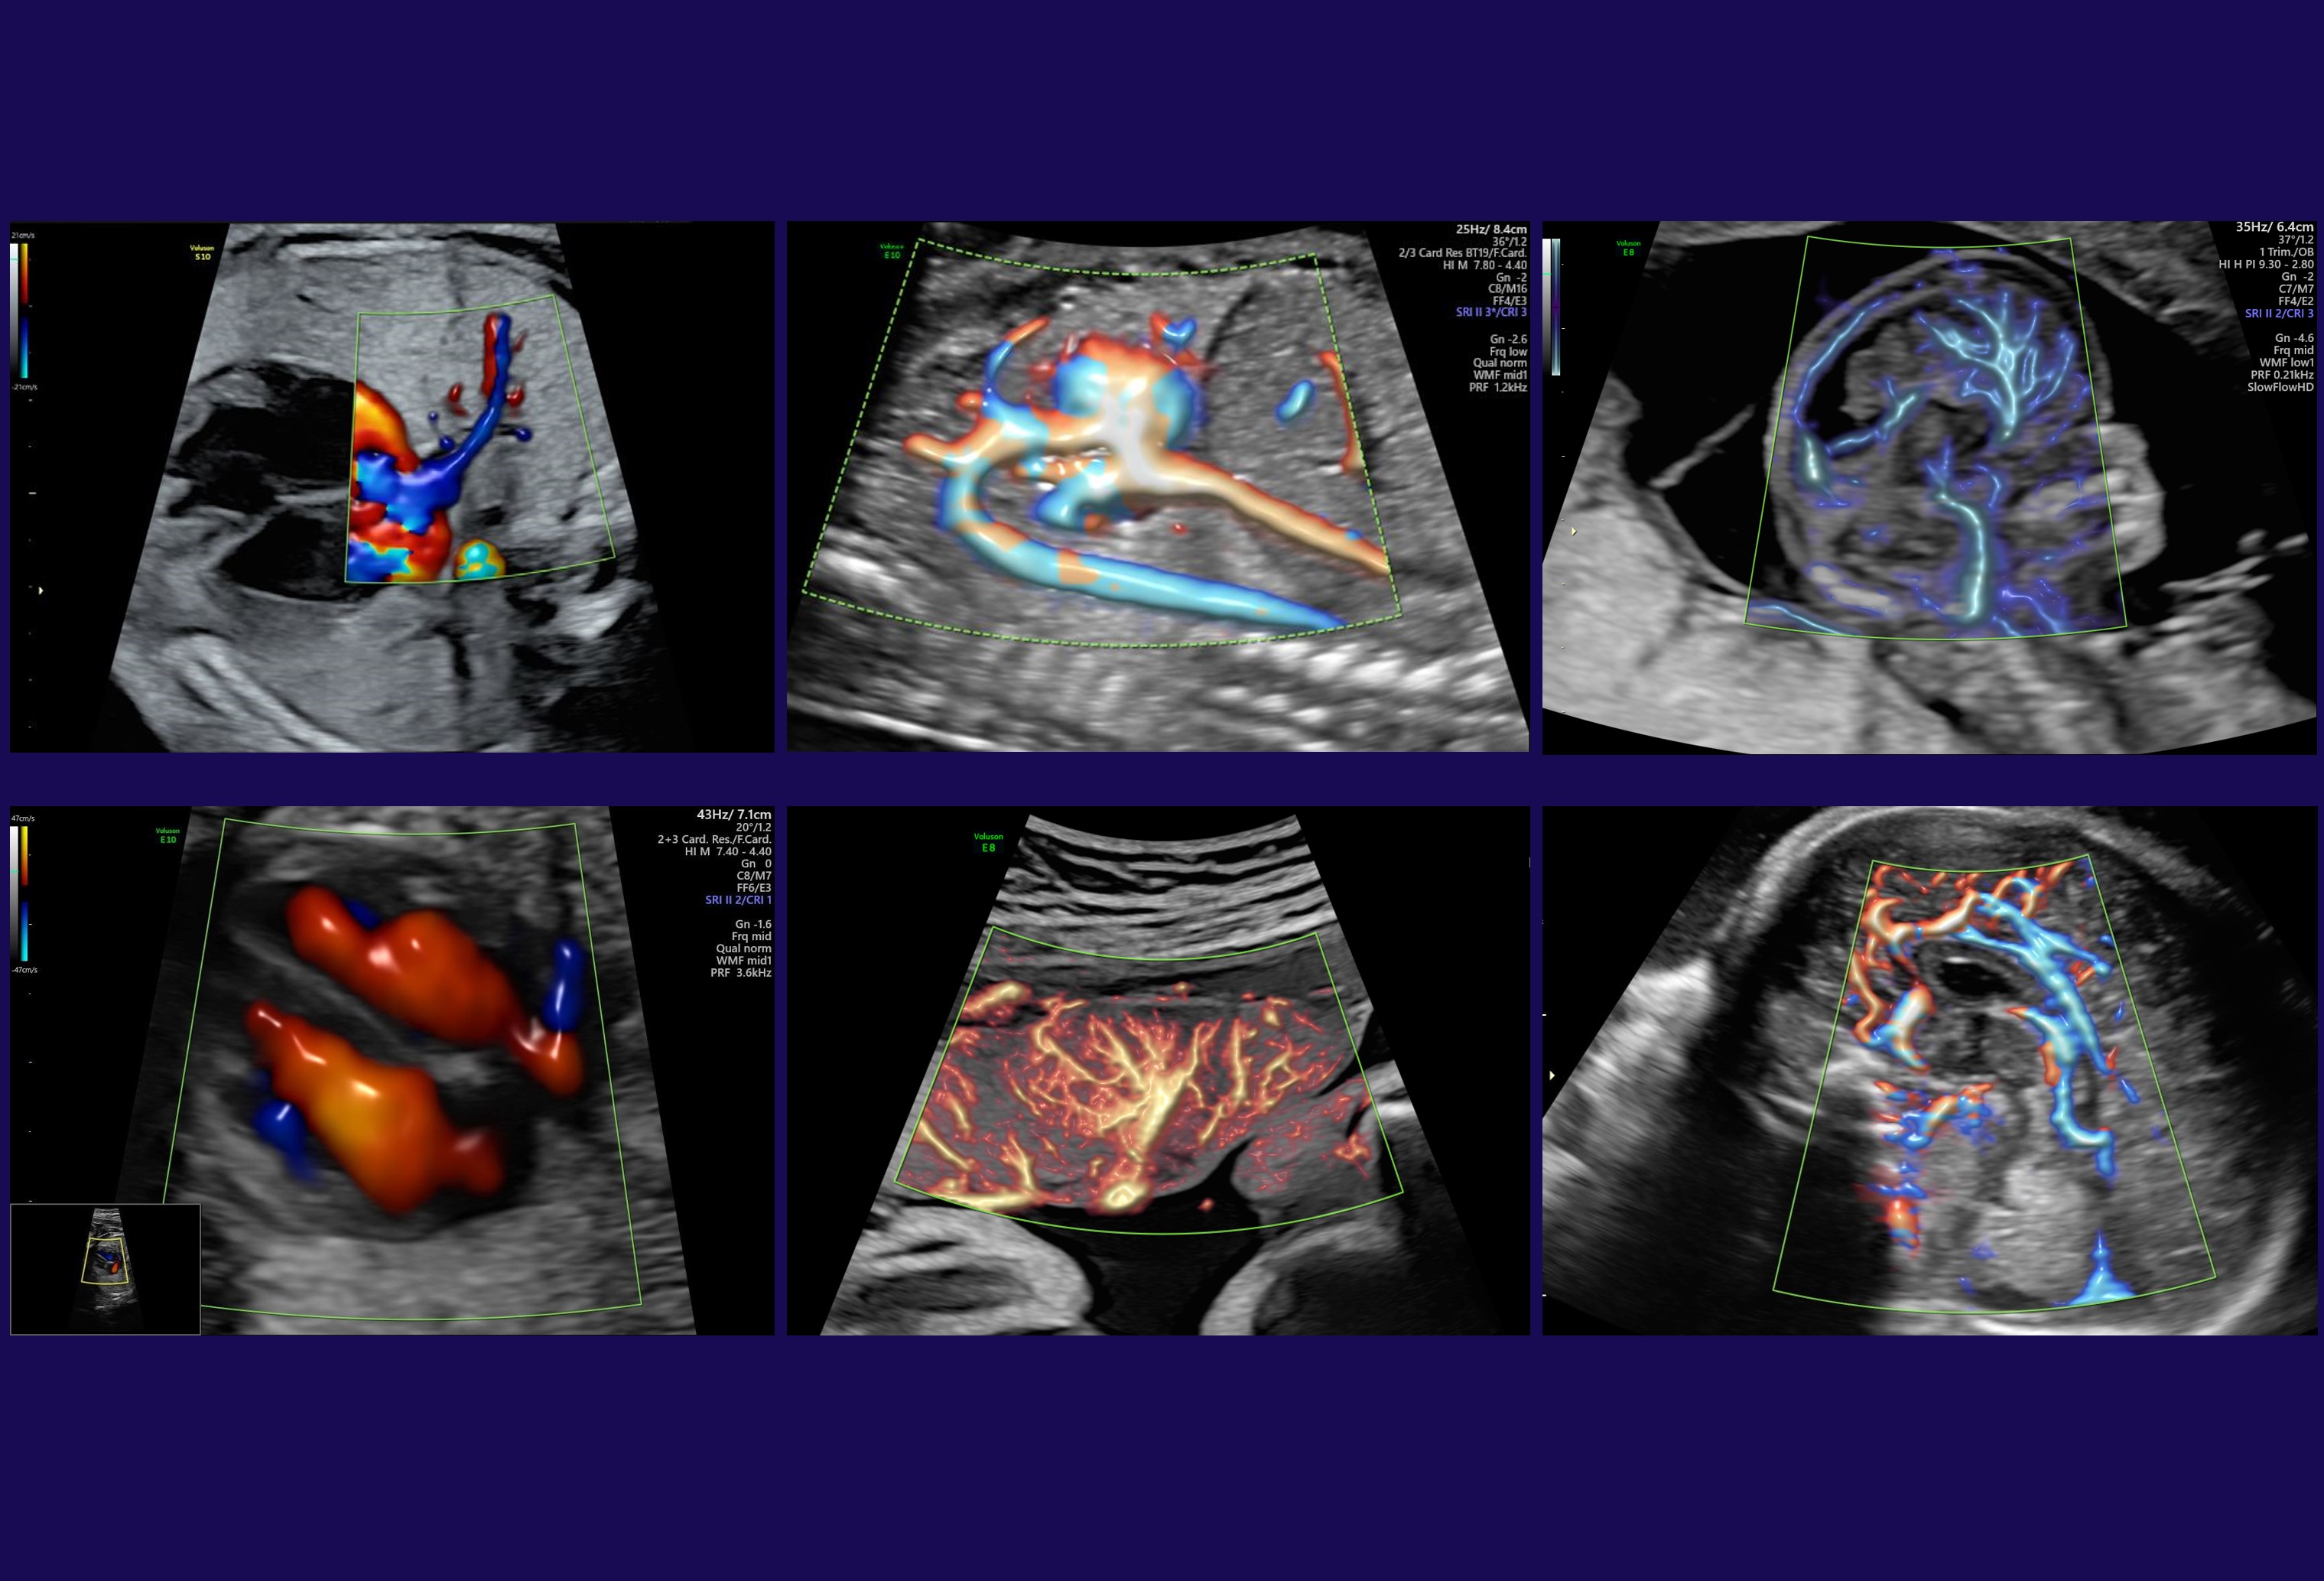

Radiantflow™

Radiantflow offre una migliore rappresentazione e una netta separazione dei vasi fornendo una maggiore percezione della dinamicità laminare del flusso sanguigno in 2D. Aggiunge informazioni di profondità e un aspetto tridimensionale e, grazie ai minori artefatti da movimento e ad una migliore definizione dei bordi, permette di identificare più facilmente e rapidamente anche i vasi più piccoli.

Radiantflow è disponibile in tutte le Modalità Color e può essere utilizzato anche in combinazione con Spettro Doppler e Color M-mode.

SlowflowHDTM

Adatto allo studio del micro-circolo, SlowflowHD può essere utilizzato anche in combinazione con Radiantflow ed utilizza entrambe le mappe Doppler mono e Bi-Direzionali a seconda delle vostre esigenze.

Applicazioni cliniche principali: cervello fetale, reni, placenta e studi avanzati di ginecologia